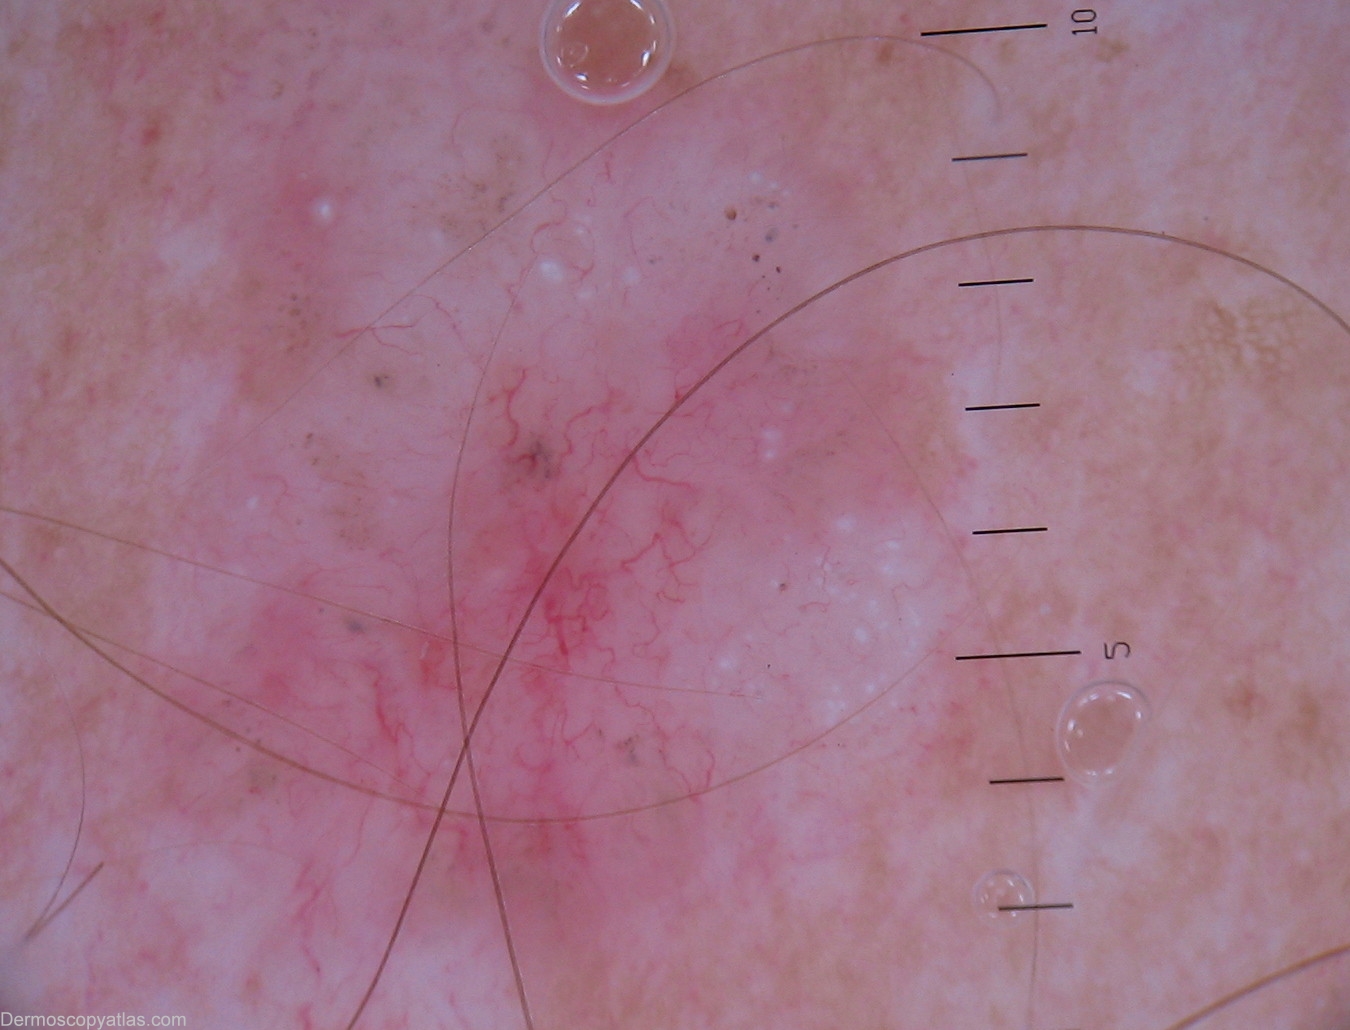

Diagnosis - BCC nodular

Diagnosis: BCC nodular